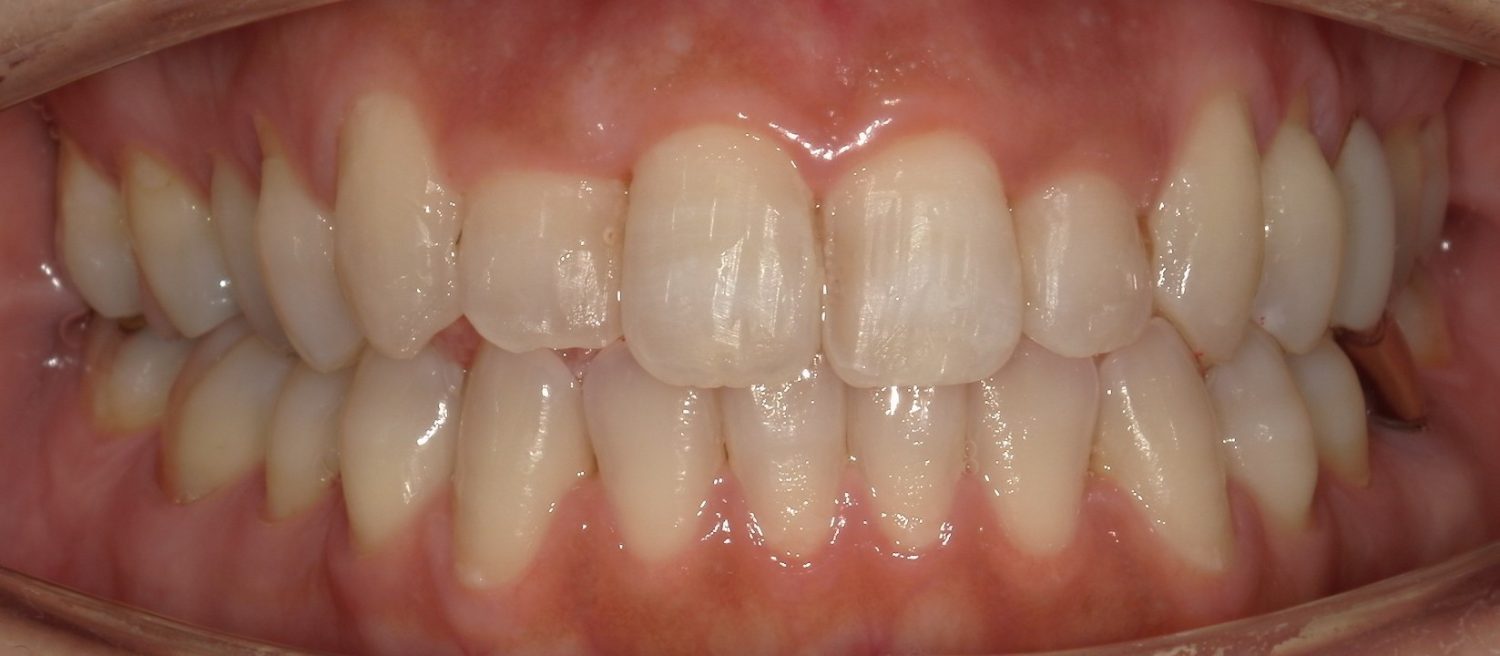

前歯だけの矯正の症例紹介①

Before

After

主訴

前歯の歯並びをキレイにしたい。

治療内容

ワイヤー矯正で治しました。

治療費

115,500円(税込)(リテーナー込み)

治療期間

2か月

通院回数

4回

想定されたリスク

※ブラックトライアングルができる可能性がありました。

多少ブラックトライアングルができたのでゴムを用いて閉鎖しました。比較的短期間で改善した症例です。